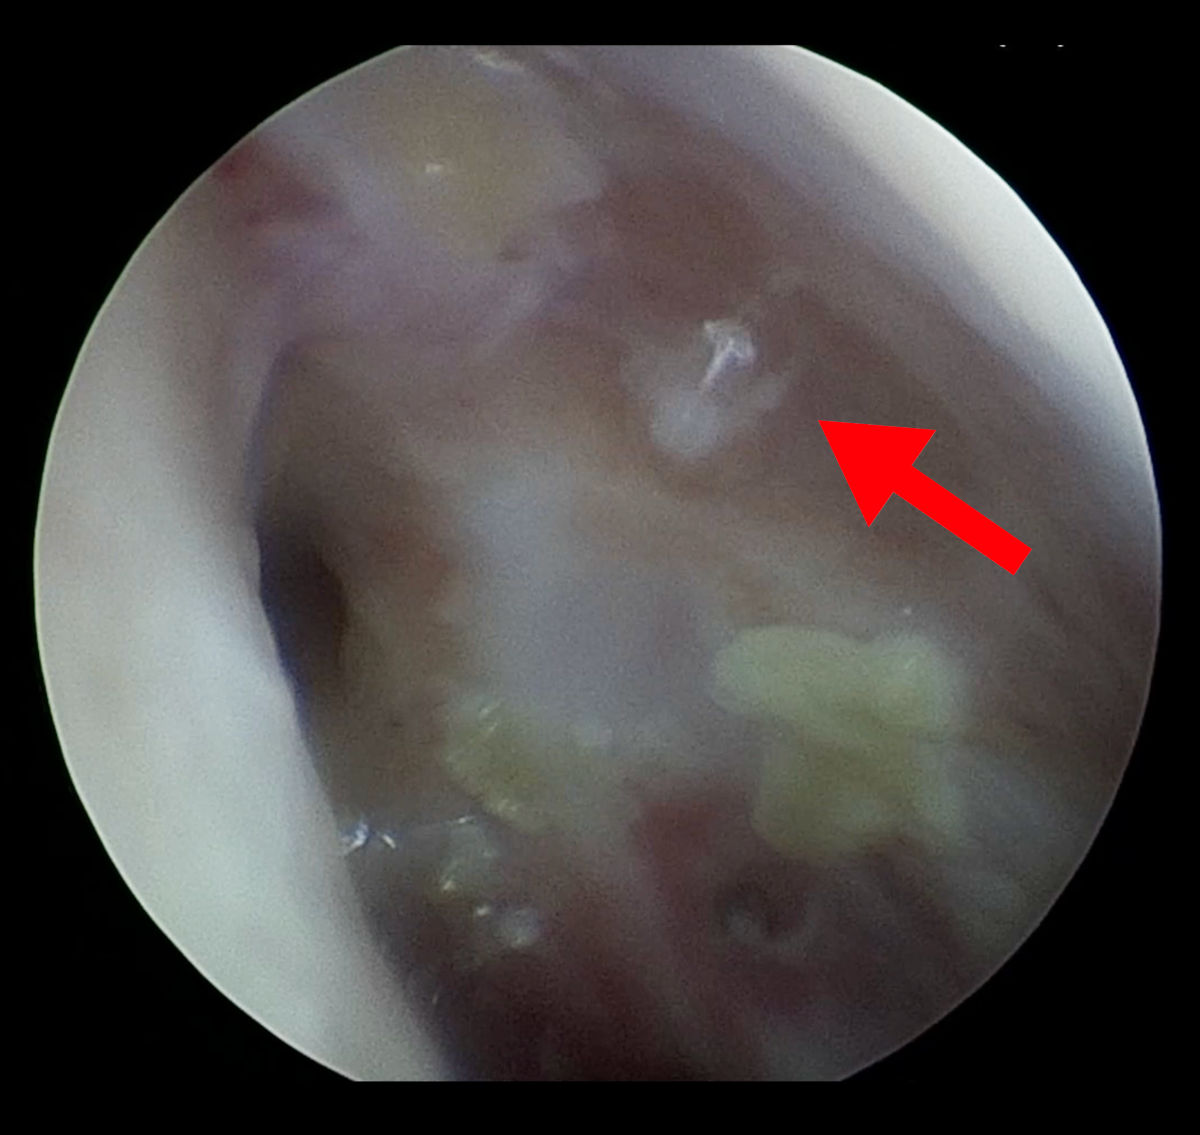

An endoscopy evaluation revealed extensive destruction with scarring in both nasal cavities (Fig 2). On the left side, a small ostium was present. It was partially patent on irrigation under pressure (Fig. 3).

Figure 2. Left side endoscopy shows extensive destruction of anatomy (S - septum, NW - nasal wall, red arrow - points at the scar after previous DCR surgery).

Figure 3. The same image as on Figure 2, note a thin trickle of fluid coming out from ostium (red arrow).